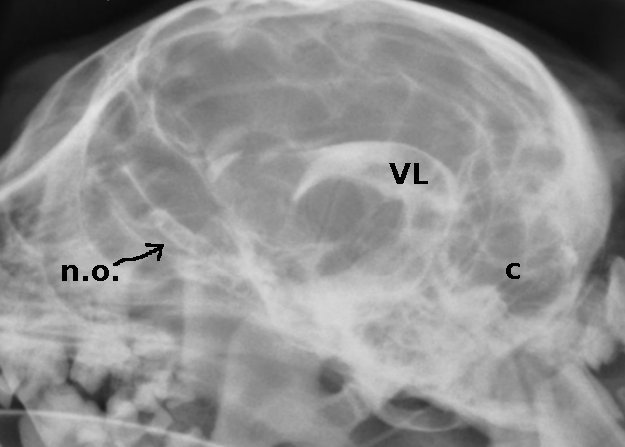

Los nervios ópticos (n.o.) y el quiasma óptico (q.o) se pueden observar en una ventriculografía (radiografía con contraste yodado aplicado en cisterna magna). Recordemos que los nervios ópticos están envueltos por meninges y por ende por líquido cefalorraquídeo.

Es fácil visualizar en la ventriculografía también el tronco encefálico (t.e)

El líquido cefalorraquídeo, presente en el espacio subaracnoideo, nos permite visualizar, gracias al contraste que contiene, el aparato ventricular (VL: ventrículo lateral) además de los surcos cerebrales y cerebelares (c).